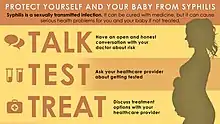

Prevention is by safe sex to prevent syphilis in the mother, and early screening and treatment of syphilis in pregnancy.[6] One intramuscular injection of benzathine penicillin G administered to a pregnant woman early in the illness can prevent congenital syphilis in her baby.[10] Treatment of suspected congenital syphilis is with penicillin by injection; benzylpenicillin into vein, or procaine benzylpenicillin into muscle.[3][9] During times of penicillin unavailability, ceftriaxone may be an alternative.[9] Where there is penicillin allergy, antimicrobial desensitisation is an option.[9][11]